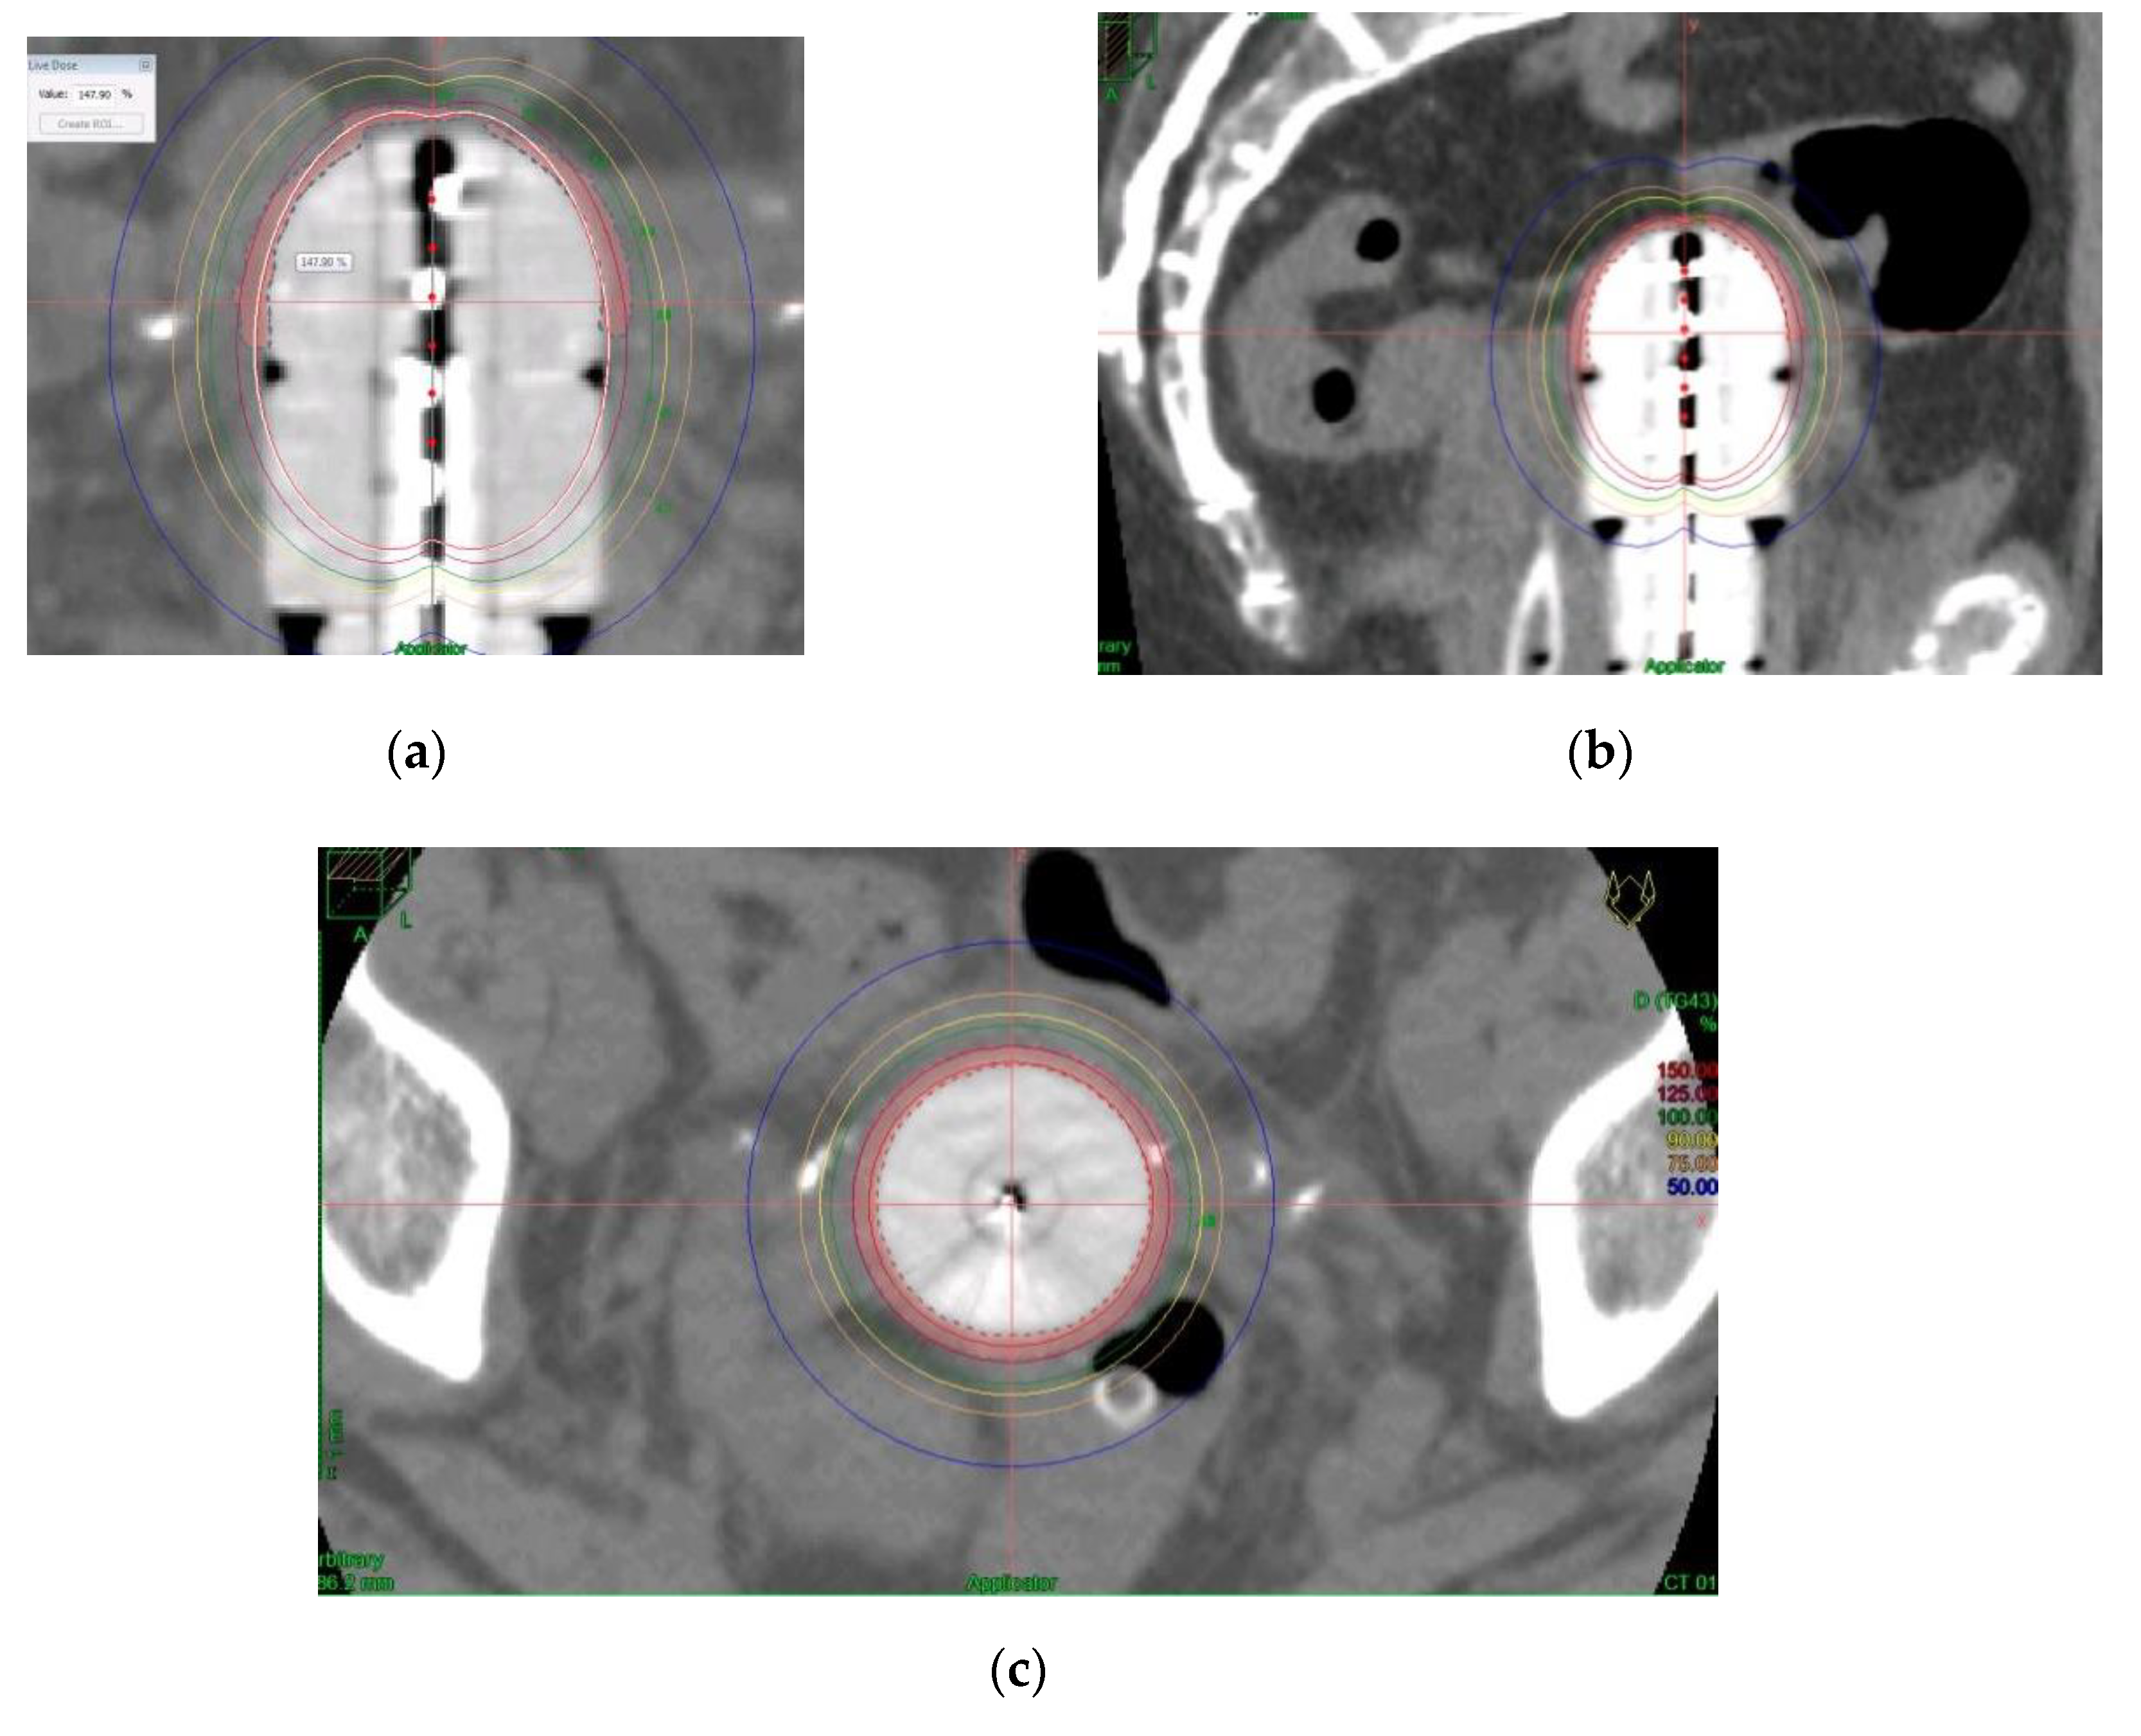

Prior to treatment, a computerized tomography (CT) simulation scan was performed with image acquisition every 1 mm for 3D planning. Special care was taken to confirm close contact of the applicator to the vagina in the CT in order to avoid relapses. Our procedure for clinical target volume (CTV) delineation consists of generating an automatic contour based on the difference in Hounsfield units of the applicator and the patient’s tissues. From this automatic contour, we generate an isotropic 3 mm margin, that is, the expansion volume. Then, a boolean subtraction of the applicator from the expansion volume is made. Finally, manual delineation of the external part of this volume is performed to adapt it to the real thickness of the vagina, which can vary depending on the case and cylinder diameter. For manual delineation, a 2 mm diameter pearl tool is used. The CTV was delineated along the first cylinder and the mean length of the postoperative treated vaginal cuff was 3cm; the rectum, bladder, and sigma were also delineated along 2 cm from the top to 2 cm under the CTV using the Oncentra Brachy planning system (V.4.5.3) (Elekta®,Nucletron BV, Veenendaal, The Netherlands). (Figure 2).

The dose was prescribed at a depth of 5 mm from the applicator surface, and point dose optimization based on distance was used. The active treatment length was 2.5 cm. In the present study, 90% of the isodose surface included the CTV. The voxels corresponding to the vaginal D2cc are always located in a small volume at the top of the vaginal-cuff and any reduction in the dose at this level will consequently reduce the dose at the prescription point. This 2cc volume is described and presented in Figure 3.

Distension of the rectum and air gaps have no impact on the D2cc of vagina considering that the 90% isodose always includes the CTV. The minimum dose of 90% received by 90% of the hottest CTV volume (D90) and the percentage of CTV coverage were calculated as well as the dose to the most exposed 2 cm3 of the rectum, bladder, and vagina. An EQD2(α/β = 3Gy) constraint of 65Gy for rectum and 80Gy for bladder were applied but were never necessary. Dose distribution was not modified to exclude the organs at risk from the dose prescription area. Figure 2 shows the dosimetric study with the area of the vagina most exposed to the dose. After dosimetric evaluation patients underwent treatment with an HDR microSelectron v2 Iridium 192 source and an afterloading source projector (Nucletron® microSelectron V3 digital ELEKTA, Holland, The Netherlands).

Figure 2. Clinical target Volume (CTV) and Organs at risk (OAR) delineation.

Cancers 12 03059 g002